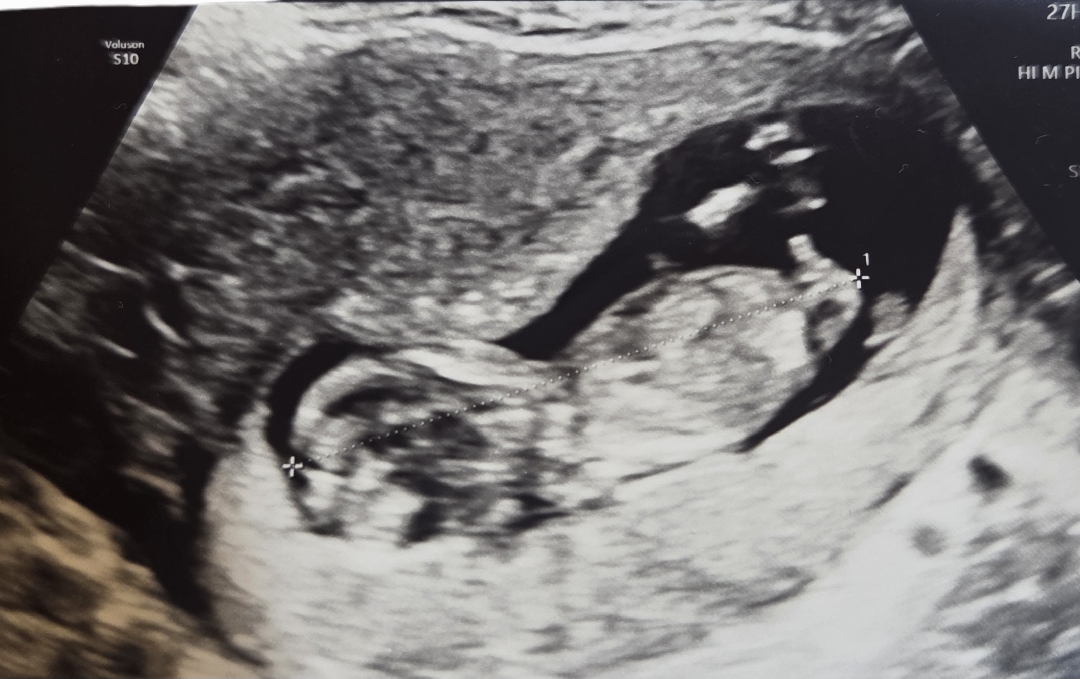

12주 4일 각도법 봐주세용:)

아들 딸 진짜 다 상관없구 다 좋은뎅ㅎㅎㅎ 궁금하긴 하네용ㅎㅎㅎ 선생님이 확률적으로 높아보이는 성별이 있긴한데 4주뒤에 확실히 알려주시겠다고 하시네용 넘 궁금해요!! 어떻게 보이시나용??

지피티가 각도법으로 추측했을 때 여아라고 해요!